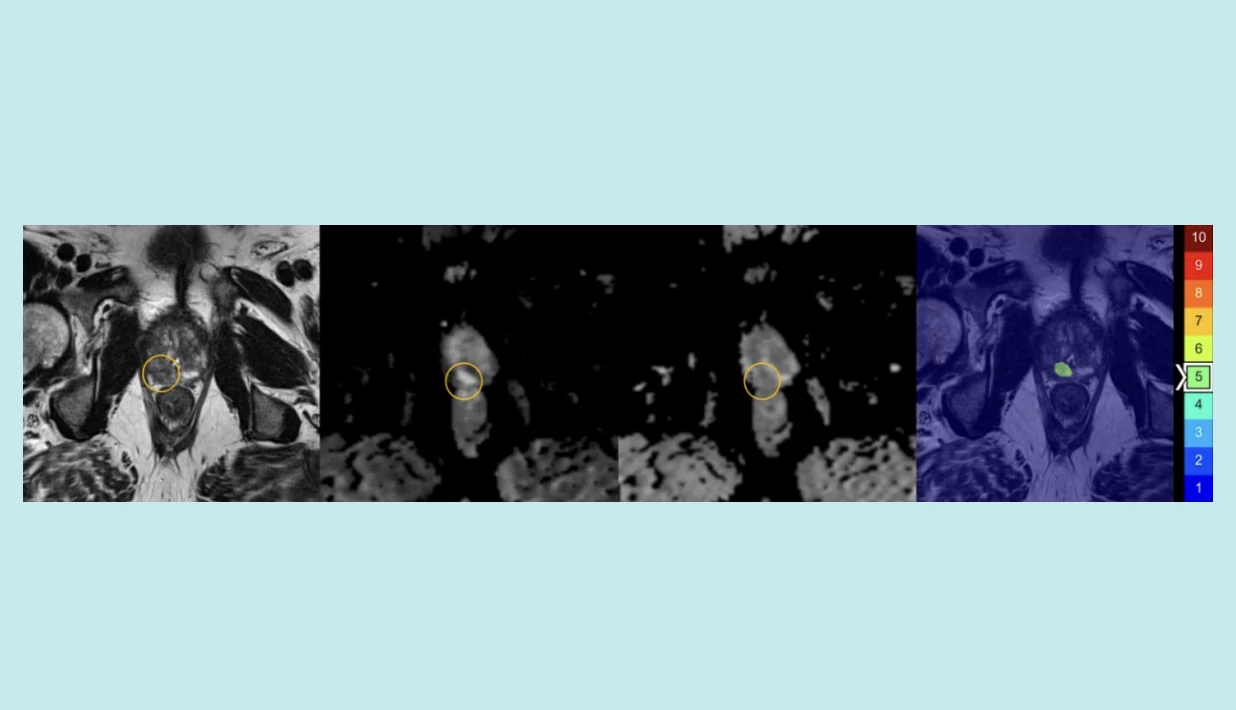

AI-assisted upgrading in the assessment

Example of AI-assisted upgrading in the assessment of a patient without clinically significant prostate cancer

Courtesy Jasper Twilt

Find prostate cancers. An AI-assisted review added to a doctor’s reading of magnetic resonance imaging improved the detection of clinically significant prostate cancer in a recent study of 360 men (median age: 65) from the international Prostate Imaging-Cancer AI Consortium. The extra reading increased detection by 3.3 percent. The algorithm is still in research.